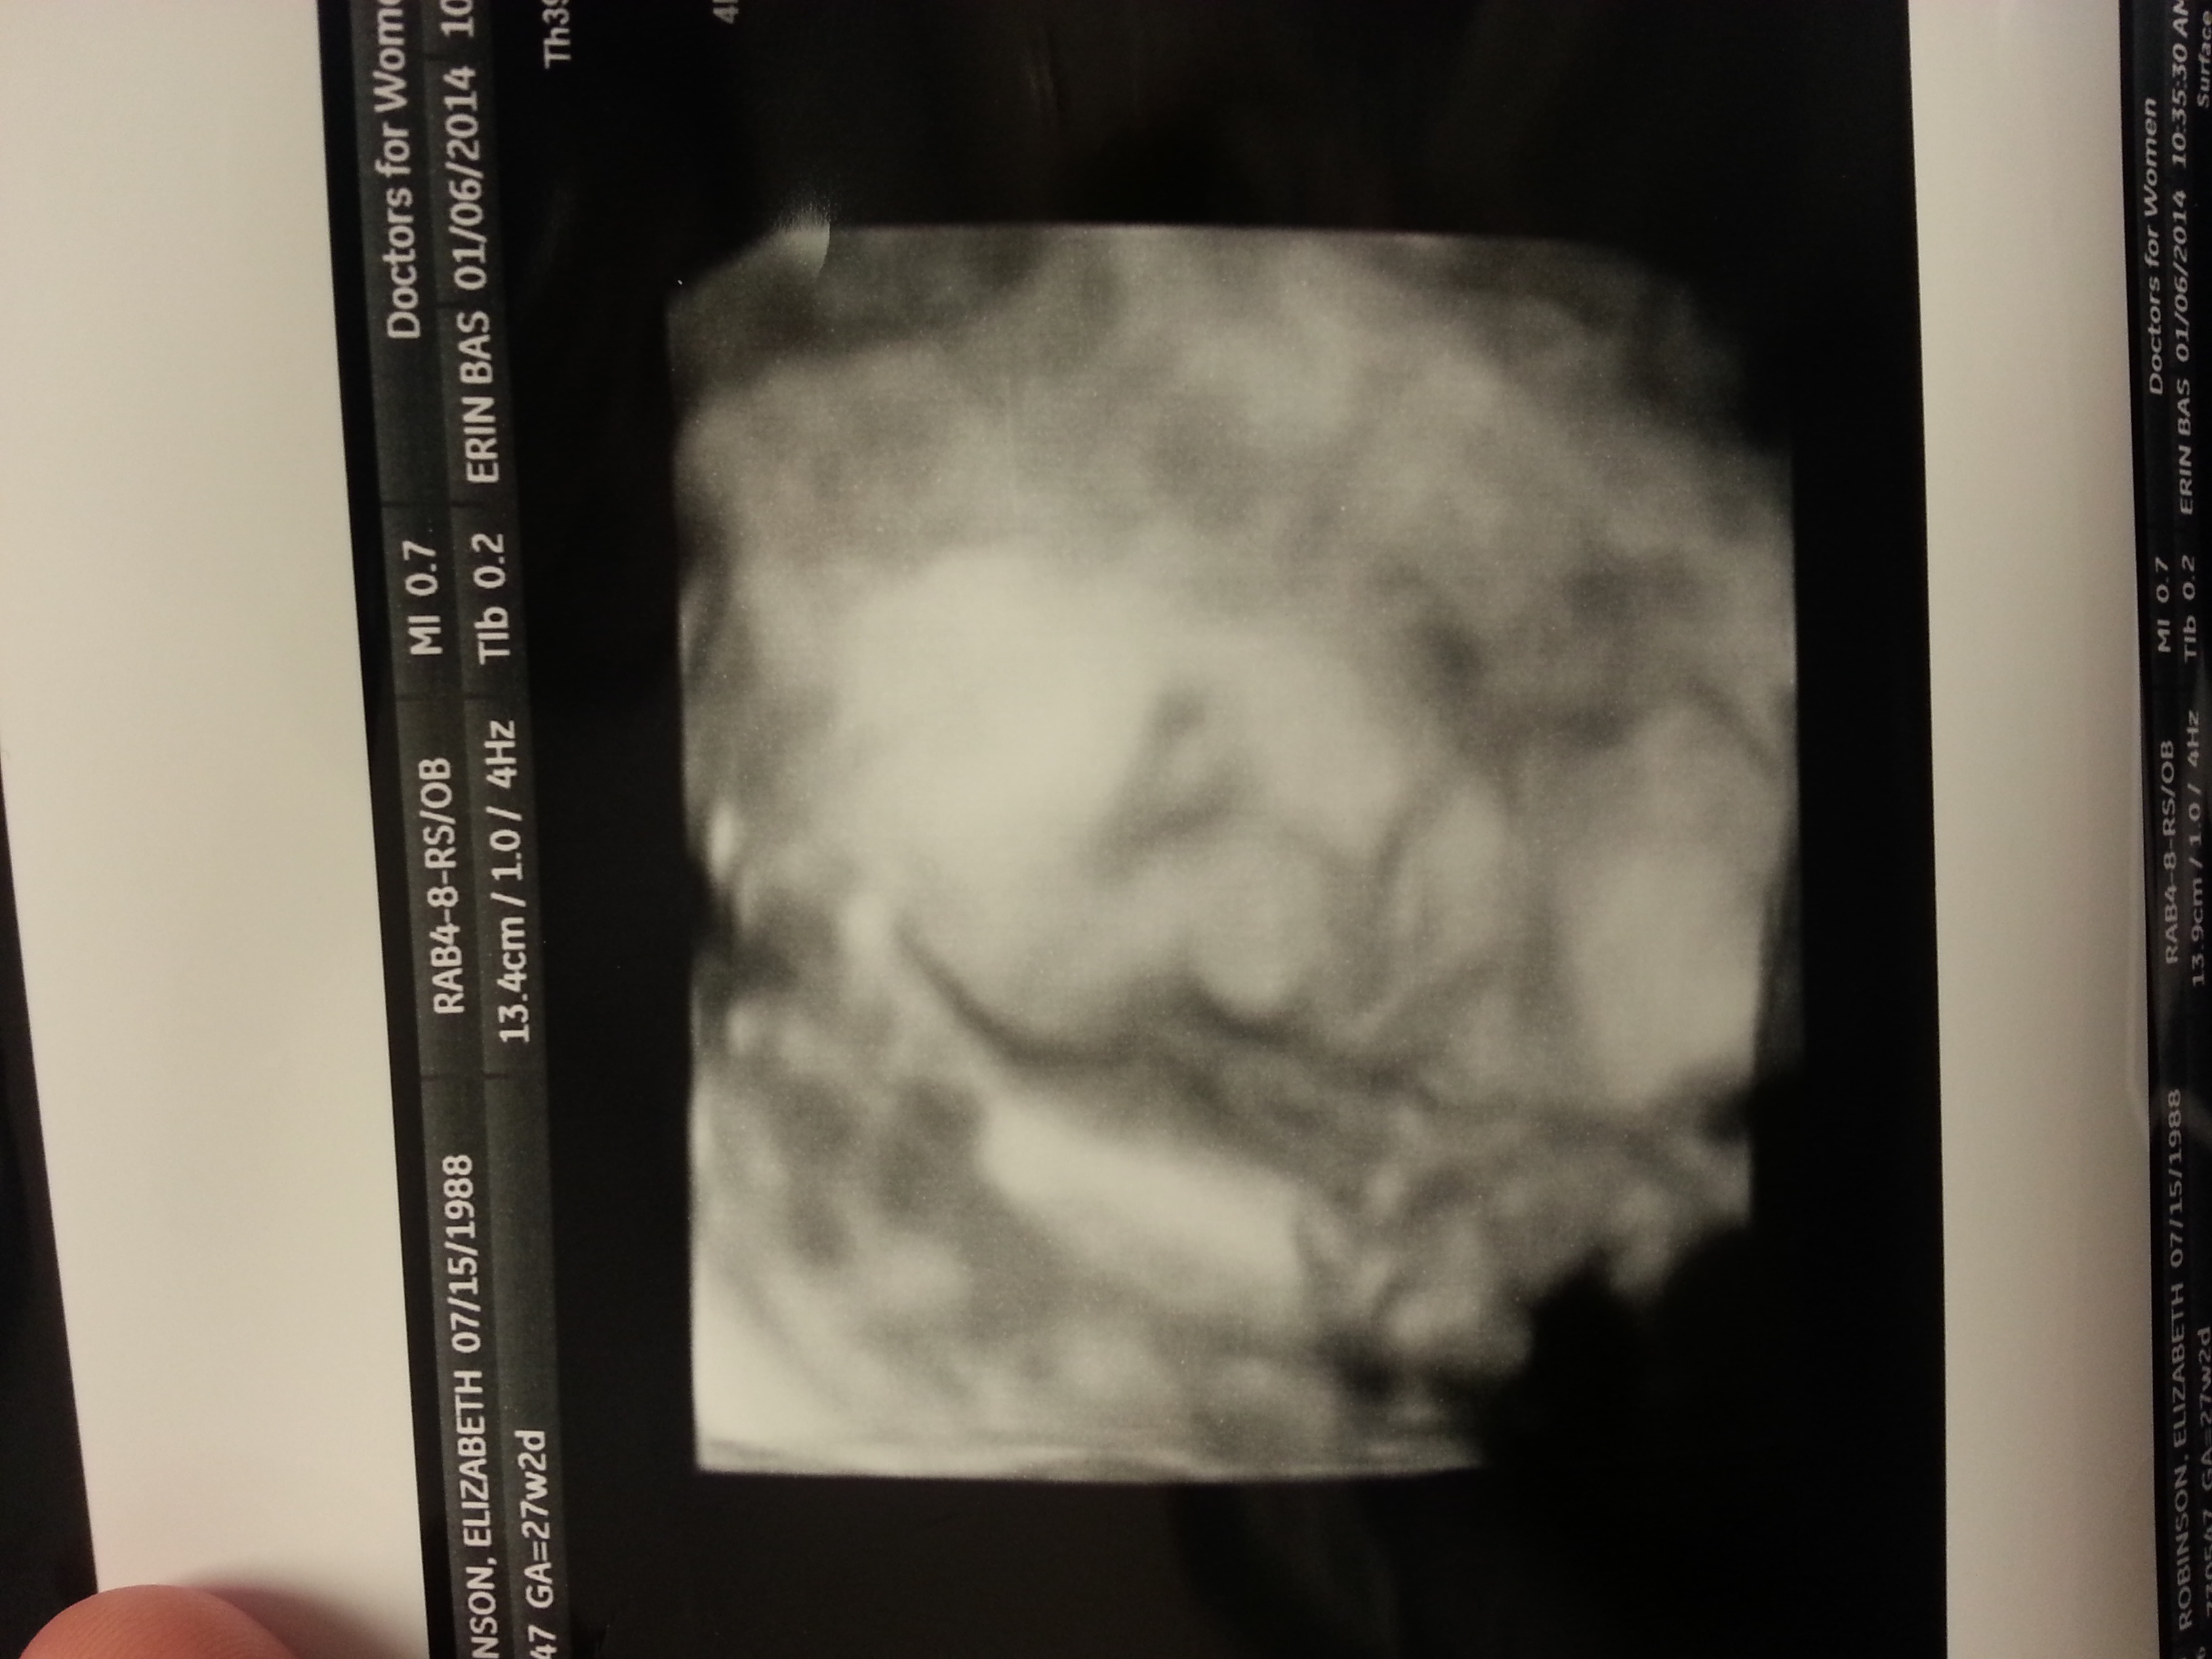

Bare belly. 26 weeks 2 days. I've grown so much over the past few weeks and even started gaining weight. Woohoo for my growing boy. You all look beautiful!